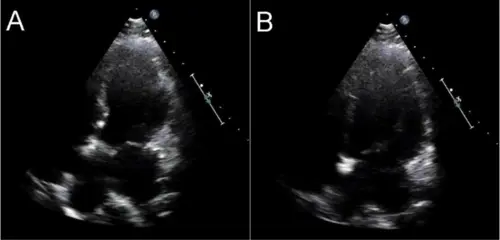

A few hours later while on 50 mcg/min norepinephrine, her HR dropped again into the 20s and another code blue was called. An official echocardiogram was performed which confirmed apical/lateral hypokinesia and an EF of approximately 30-35% (Figure 3).

Figure 3. Representative static images from the cardiac ultrasound.

Panel A: systole. Panel B: diastole.1 Courtesy: Dr. Schmitz